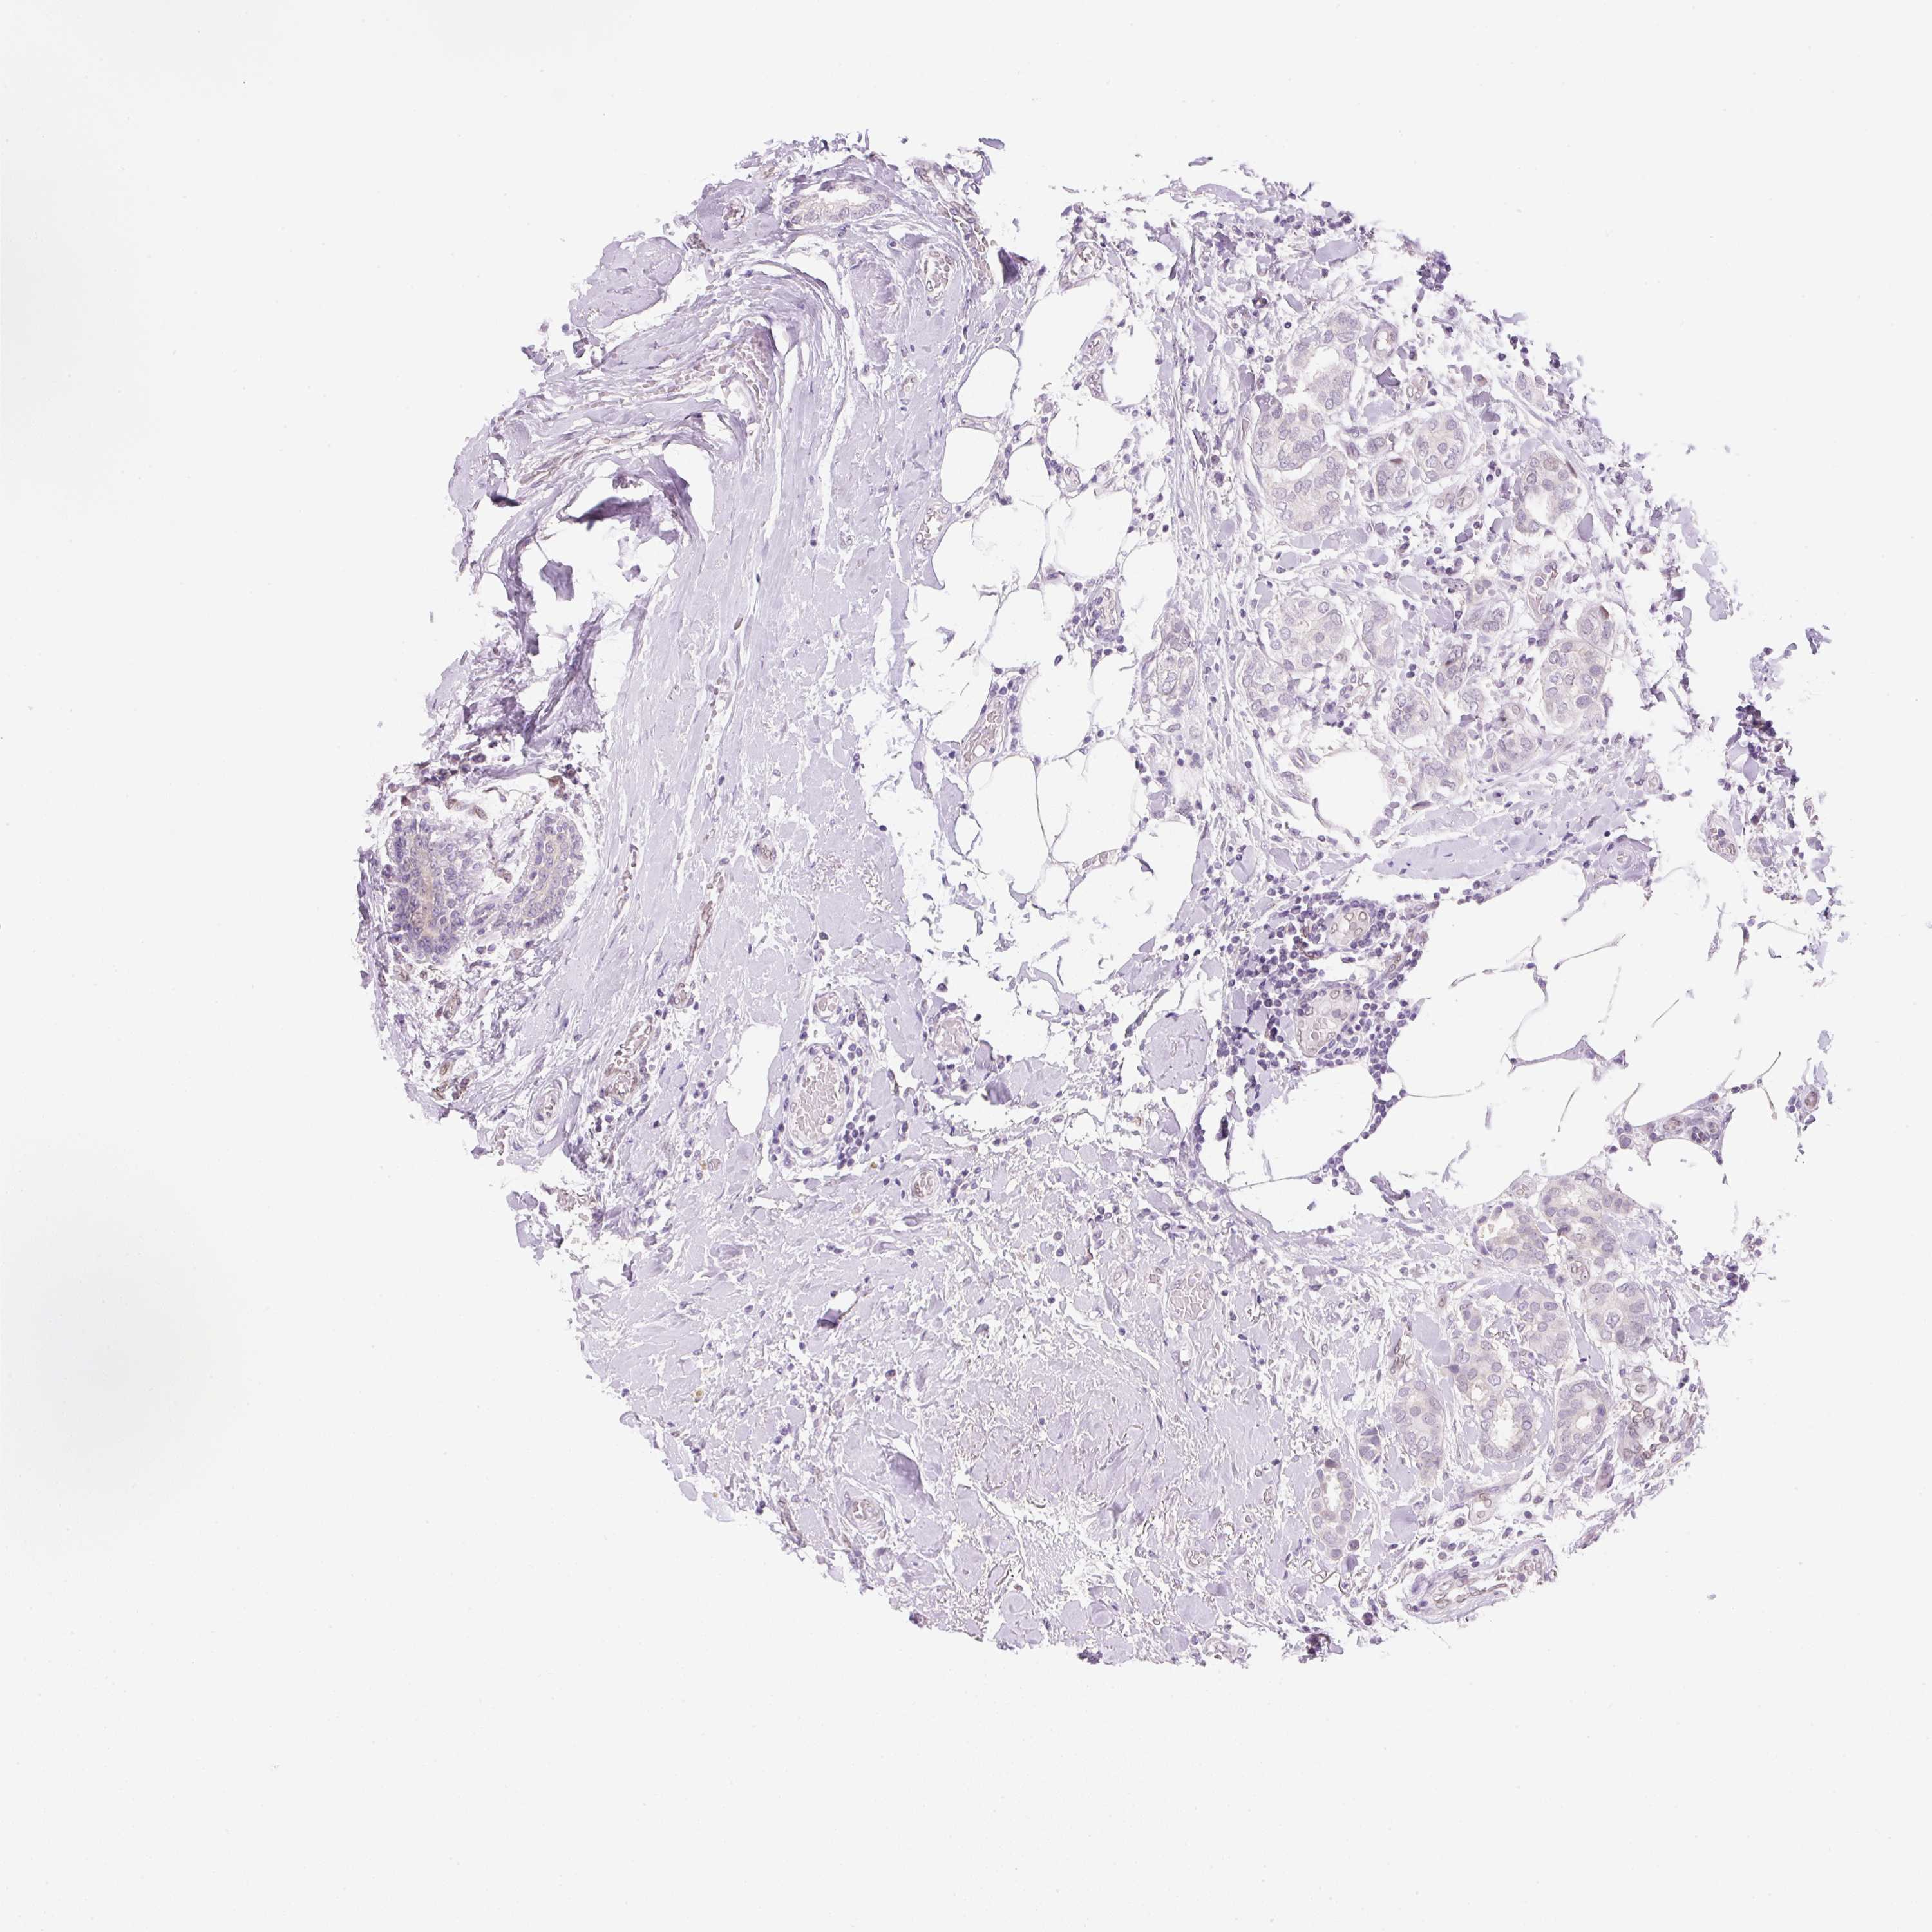

Breast cancer

Human cancer

CANCER BREAST CANCER Show tissue menu